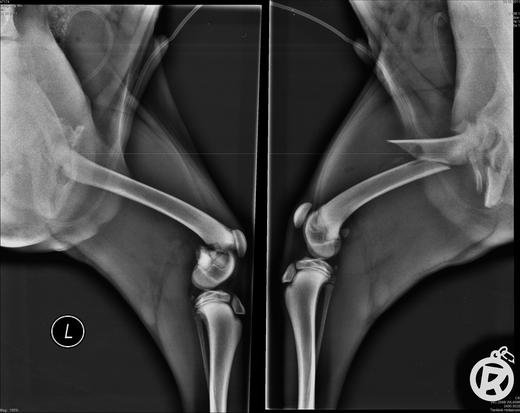

狗才四個月太小,因此要分兩次開刀,第一天是開後面兩條骨折的腿,大腿上各放了兩個固定鐵片.

骨盆腔裡面放了特殊的伸縮螺絲;第四天狗才能出院.